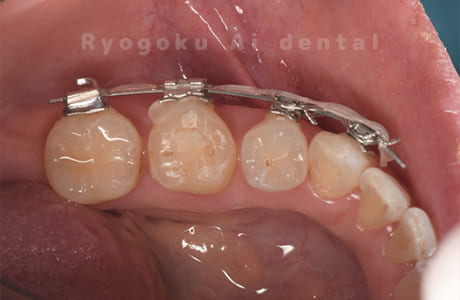

Case27

-

重度カリエス

歯牙移植咬合面術前 -

移植する親知らず

歯牙移植術直後咬合面

歯牙移植術後咬合面

歯牙移植術前側面

歯牙移植術中側面

歯牙移植術後側面

部分矯正術前咬合面

部分矯正術中咬合面

部分矯正術後咬合面

部分矯正術前側面

部分矯正術中側面

部分矯正術後側面

- 原因

- 重度カリエス

- 治療内容

- 自家歯牙移植、部分矯正

- 治療費用

- 220,000円(移植費用)

110,000円(部分矯正費用)

虫歯が大きく、保存不可能となった歯を上の親知らずと交換する自家歯牙移植を行いました。移植歯が小ぶりであったため、部分矯正を行い問題なく噛み合い、経過良好です。

<リスク・副作用>

治療後、痛みや違和感、出血、腫れなどが出る事があります。喫煙者、糖尿病などの方の場合、歯が生着しない場合があります。